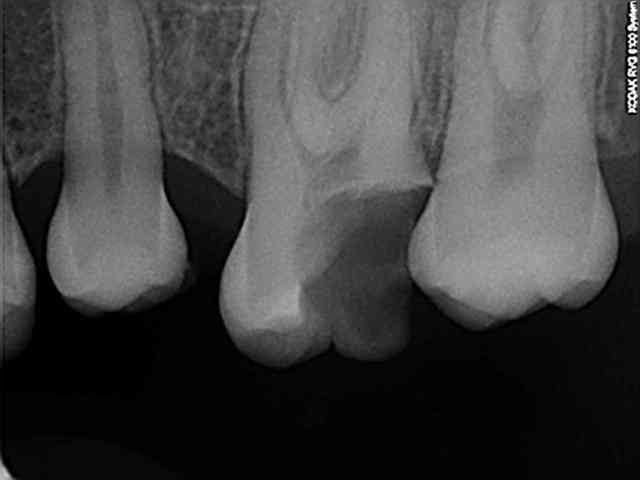

j'ai presque honte de vous montrer ce cas, mais je pense qu'il pourrait être utile de partager cette expérience avec vous.

je viens d'acheter récemment du ciment d'obturation canalaire en seringue avec un embout très fin pour injecter directement dans les canaux (dixit le commercial).

je l'essai donc avec sucés depuis 3 ou 4 semaines, mais là aujourd'hui, j'ai poussé trop fort sur la seringue et voilà le résultat; j'ai immortalisé les vaisseaux sanguins de la patiente.!!!

Je me trompe ou c'est sur un seul canal que tu as appuyé un chouia trop fort et c'est celui là qui t'a fait ce magnifique dripping à la Jackson Pollock ? Et puis, bon, les canaux accessoires et secondaires sont tops...:)

Bon, tout ça pour dire qu'il ne faut pas injecter directement dans les canaux.

Je ne mets pas en cause le produit, mais je vous invite à faire attention, sinon, les résultats en endo sont plutôt très bon.